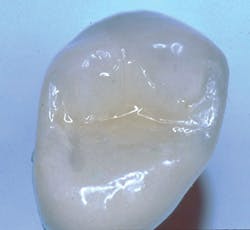

Recently, dentists and laboratory technologists have asked themselves why they were making separate abutments when many clinical situations allow use of a three-piece combination (implant, crown, and a screw through the crown into the implant) without a separate abutment. (Figs. 1-3)

FIG. 2 -- Crown on working cast. Note screw to be placed in hole through crown. Some patients object to the discoloration of the occlusal surface caused by the screw hole. Suggestions on how to restore the hole are included in this article.

This article discusses why the three-piece concept is often better than the four-piece, when it cannot be used, how best to hide the esthetically unacceptable hole necessary for screw access, and what to do when the screw comes loose from the two-piece implant crown combination.